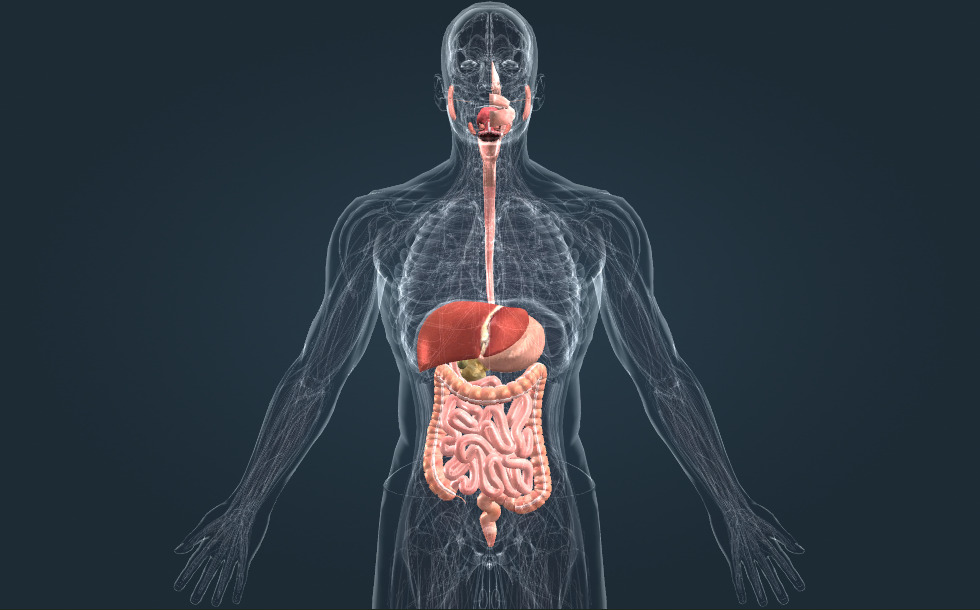

Spijsverteringsstelsel

- maag - Eiwitten worden verteerd in dit orgaan. Maagsap is erg zuur.

- dunne darm - Eiwitten, koolhydraten en lipiden (vetten) worden verteerd in dit orgaan. Verteerde voedingsstoffen worden hier geabsorbeerd.

- dikke darm - Water en mineralen worden hier verteerd. De bacteriën in de darmflora produceren vitamine K en B.

- rectum

- lever - Speelt een belangrijke rol bij de ontgifting van het bloed en produceert het gal dat de afbraak van vetten (lipiden) ondersteunt.

- alvleesklier - Produceert pancreassap dat vetten, koolhydraten en eiwitten verteert in de dunne darm. Het scheidt ook het hormoon insuline af. Insuline verlaagt het glucoseniveau in het bloed.

- slokdarm

- mondholte

- galblaas - Een hol, peervormig orgaan waarin de gal tijdelijk wordt opgeslagen. Tijdens de opslag wordt de gal geconcentreerd.

Het maagdarmstelsel is verantwoordelijk voor de vertering en absorptie van voedingsstoffen.

Voedsel wordt vermalen in de mond door de tanden; daarna kan de vertering van koolhydraten beginnen. Eiwitten worden verteerd in het zure maagsap. Daarna worden er in de dunne darm drie soorten voedingsstoffen opgenomen: eiwitten, koolhydraten en lipiden. Alvleeskliersap wordt afgescheiden door de alvleesklier en bevat spijsverteringsenzymen die daar afgegeven worden. Gal, dat wordt uitgescheiden door de lever, helpt bij de vertering van vetten. De dikke darm absorbeert water en mineralen; zijn darmflora produceert vitaminen.

Het maagdarmstelsel is verantwoordelijk voor de vertering en absorptie van voedingsstoffen.

Voedsel wordt vermalen in de mond door de tanden; daarna kan de vertering van koolhydraten beginnen. Eiwitten worden verteerd in het zure maagsap. Daarna worden er in de dunne darm drie soorten voedingsstoffen opgenomen: eiwitten, koolhydraten en lipiden. Alvleeskliersap wordt afgescheiden door de alvleesklier en bevat spijsverteringsenzymen die daar afgegeven worden. Gal, dat wordt uitgescheiden door de lever, helpt bij de vertering van vetten. De dikke darm absorbeert water en mineralen; zijn darmflora produceert vitaminen.